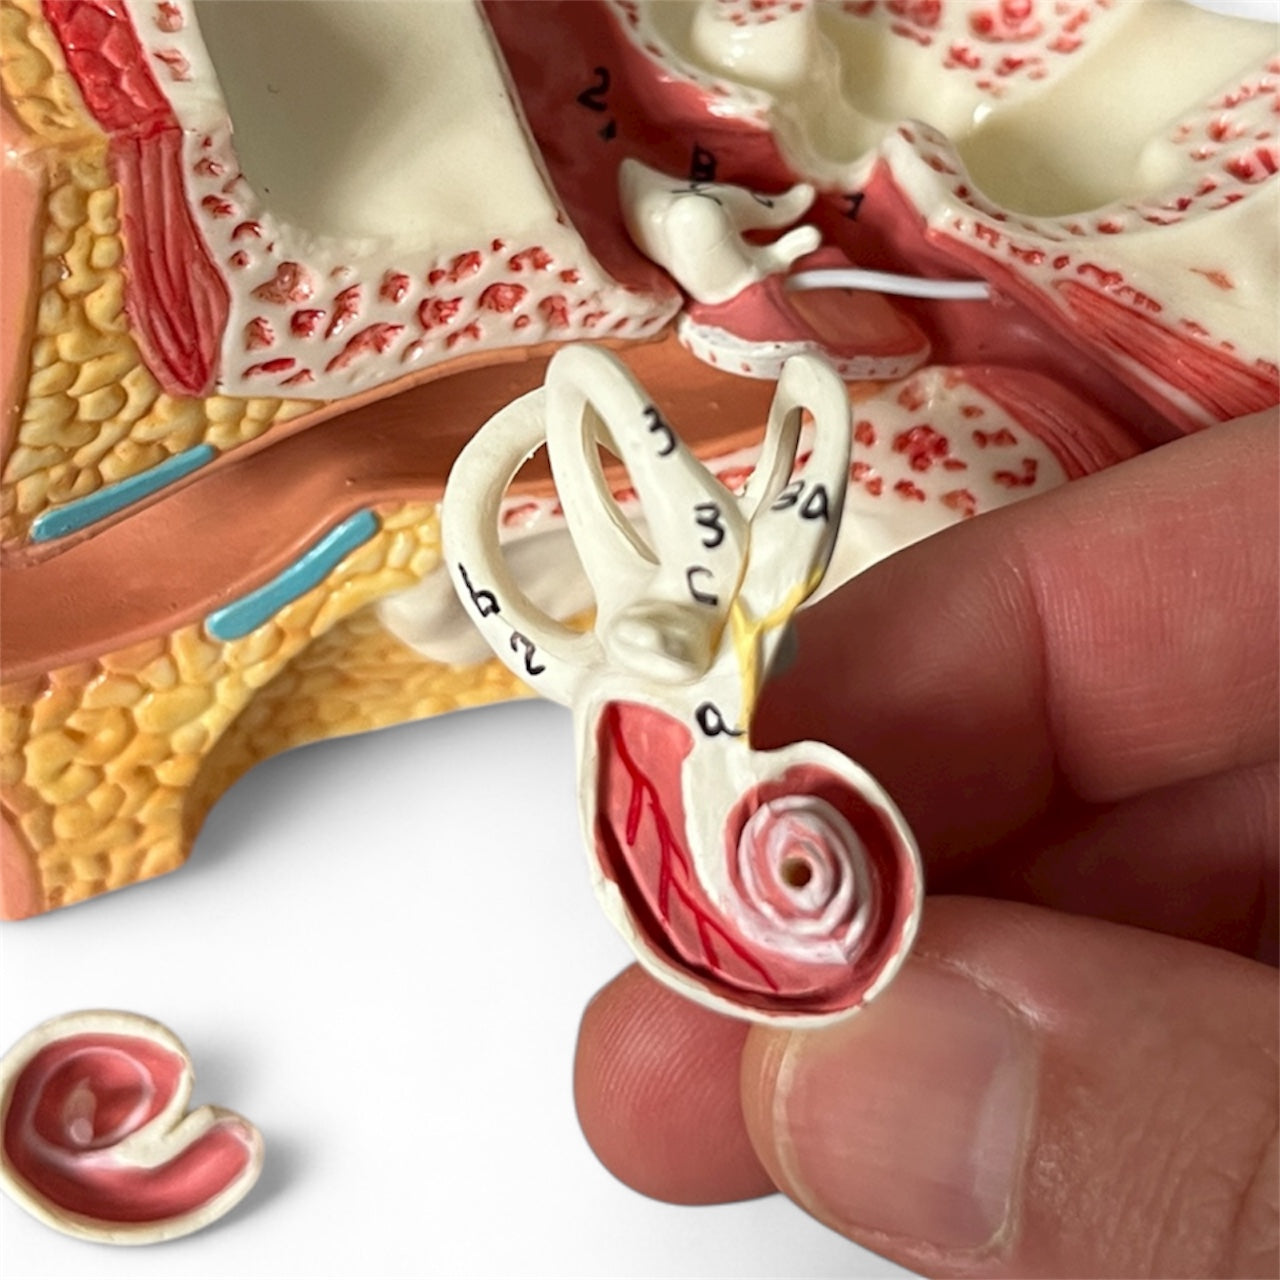

Selling anatomical models is the mainstay of eAnatomi, although we also spend a lot of resources developing our own anatomical materials such as posters. Anatomical models are used for various purposes and can show both defined tissues, organs and organ systems. Are you looking for a simple model of bone tissue or perhaps an advanced torso model based on MRI technology, you can find it all at eanatomi.com.